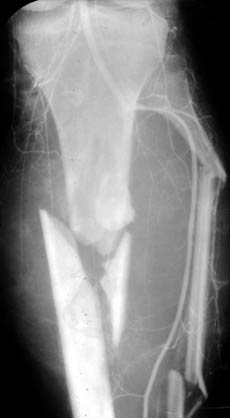

Диагностика острой и хронической патологии артерий конечностей.

Рис. 3. Травматическое повреждение сосудов голени.